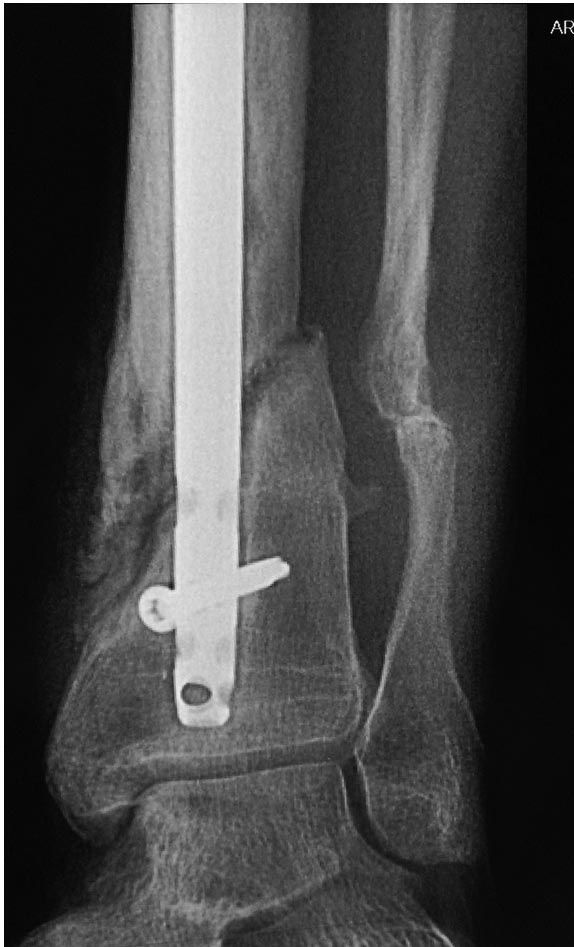

Уважаемые коллеги выразите Ваше мнение по следующему случаю.Молодой человек, 27 лет, находится на лечении с диагнозом: Ложный сустав большеберцовой кости в нижней трети, фиксированный интрамедуллярным блокированным стержнем (12.02.2014 г), ложный сустав малоберцовой кости в нижней трети левой голени, посттравматический артроз левого голеностопного сустава 1 стадии. Укорочение левой нижней конечности на 1,0 см. Со слов пациента известно, что в детстве получил перелом большеберцовой кости, лечился консервативно, перелом сросся с деформацией. Травма в июле 2010 г. бытовая-упал на лестнице, получил перелом малоберцовой кости, и перелом большеберцовой кости без смещения. Выполнена операция: Остеотомия большеберцовой кости в нижней трети, интрамедуллярный блокированный остеосинтез большеберцовой кости левой голени. Гладкое течение послеоперационного периода. Перелом большеберцовой кости сросся. Функция конечности восстановилась. В июне 2013 г выполнена операция удаление интрамедуллярного стержня из большеберцовой кости левой голени. Гладкое течение послеоперационного периода. Приступил к занятием физкультурой, бег. В августе 2013 г спрыгнул с автобуса, с чемоданом в руках, появилась резкая боль в левой голени. За медицинской помощью обратился через 7 дней, при обследовании выявлено: Рефрактура большеберцовой кости. Рекомендовано консервативное лечение в гипсовой повязке. В январе 2014 г. установлен диагноз: Ложный сустав большеберцовой кости в нижней трети, малоберцовой кости в нижней трети левой голени. Контрактура сгибательно - разгибательная левого голеностопного сустава. Посттравматический артроз левого голеностопного сустава 1 стадии. Укорочение левой нижней конечности на 1,0 см. В феврале 2014 г выполнил первым этапом: Фиксацию ложного сустава в АНФ с восстановлением осей сегментов. Через семь дней БИОС с рассверливанием. После операции - вальгус голеностопного сустава. Гладкое течение послеоперационного периода. Нагрузка по переносимости боли. Через 6 недель динамизация, через 2 недели стали мигрировать 2 фронтальных винта. Пытался подкрутить, пришлось удалить. Через 6 мес., контроль - линия ложного сустава прослеживается, но имеется периостальная костная мозоль. Не хватает стабильности.Вопрос что делать?Вариант № 1- выполнить реостеосинтез с рассверливанием КМК и на 12 мм диаметра гвоздь (стоит 11 мм)и убрать ротацию стопы руками одномоментно или одномоментно при помощи АНФ во время операции. Вариант № 2 выполнить удаление гвоздя, сделать все то же, что 6 месяцев назад, но с восстановлением анатомических взаимоотношений в голеностопном суставе.Вариант № 3 Двухэтапно, вторым этапом пластина на большеберцовую кость + костная пластика области не сращения.Вариант № 4 удаление гвоздя и лечение в КДА. Вопросы:1. Какой вариант оперативного лечения будет оптимальным в данном случае.2. При двухэтапной методике в дистальном отломке имеется канал от гвоздя, как направить гвоздь к наружному отделу дистального отломка большеберцовой кости. Есть опасения, что гвоздик может пойти по тому же каналу. Использовать поллер спицы или винты – сработают ли? И достаточна ли будет жесткость фиксации дистального отломка большеберцовой кости на гвоздике при 3 – 4 винтах при реостеосинтезе гвоздем.3. Нужен ли остеосинтез малоберцовой кости в нижней трети, с целью создания латеральной опоры. К сообществу за советом.

Александр Николаевич спасибо за ответ. Три снимка перед внешним видом конечности крайние. На одном из них левая стопа в положении внутренней ротации 15 градусов.

Из предложенных, я бы остановился на третьем варианте. Основная работа должна быть против вальгуса, и медиальная пластина для этой роли не подходит. Передний доступ, остеотомия большой и малоберцовой. Сагиттальная пила для артропластики толстая и не экономит кость. Полотно не более, чем 1.1 мм толщиной, создает идеальную поверхность остеотомии. Затем боковая компрессия-лагированием и передная пластина с костным графтом! Возможно, потеряет часть высоты, но наконец то возникнет сращение!